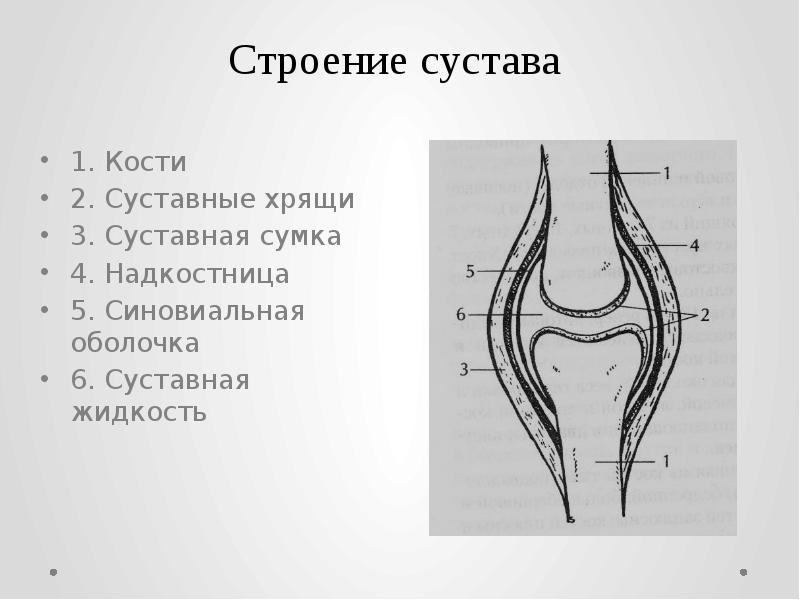

Рисунки Суставов: Анатомические Иллюстрации

Раздел: Мозаика смыслов